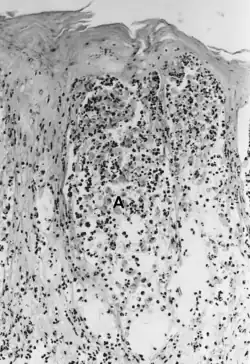

![]() Akantolýza u slintavky a kulhavky ve vzorku váčku z kůže. Lze si povšimnout, nekrózy vrstvy Stratum spinosum a keratinocyty plovoucí v tekutině váčku (spongiosa). | |

Akantolýza je ztráta mezibuněčných spojů mezi keratinocyty v horní vrstvě pokožky. Vytvoří se puchýř naplněný mezibuněčnou tekutinou s uvolněnými keratinocyty. Najdeme ji například u vzácného onemocnění Pemphigus vulgaris.